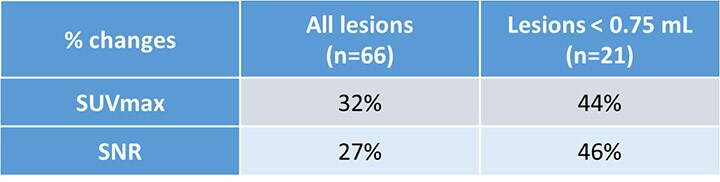

Sharper images with profound increase in SUV and SNR for small lesion detection

Study points out physician preference for 2 mm voxel image reconstruction in detecting small lesions

A recent study, carried out by clinicians at Isala and published in the Journal of Nuclear Medicine Technology, showed physician preference for using the 2 mm voxel reconstructions on the Ingenuity TF PET/CT system to detect small lesions in FDG-PET exams. In the study, FDG PET scans of two image-quality phantoms (sphere sizes 4-37 mm) and 39 consecutive patients with lung cancer were analyzed. The authors found a profound increase in SUV and signal-to-noise ratios (SNRs) for small lesions using a small 2 mm voxel reconstruction. See results in table below.

The physicians in the study preferred the small voxel reconstructions in 76% of the cases.